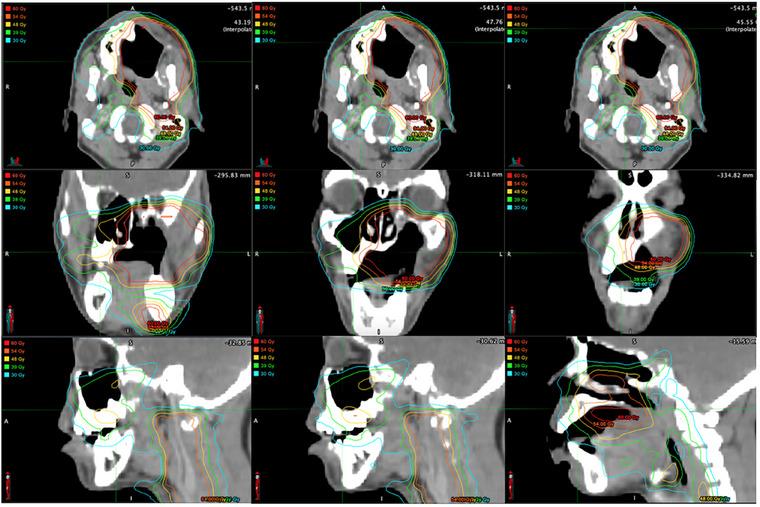

A Targeted Approach to Dental Treatment for Patients Prior To and After Head and Neck Radiation.

This is a narrative review of contemporary radiotherapy for head and neck cancers, the role of pre-radiation dental clearance, and rationale for a targeted approach to pre-radiation treatment. Emphasis is placed on avoiding delay in the start of radiation. The goals of this article are to facilitate communication between the dentist and radiation oncologist, succinctly summarize current recommendations, and give suggestions on what qualifies as high priority dental care in the pre-radiation setting.